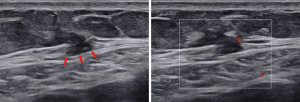

When a fracture occurs, it manifests as a space, step, or displacement within the rib cortex. Fractures may be associated with local hematoma, fluid accumulation, or soft tissue swelling. During the acute healing phase, enhanced echogenicity indicative of callus formation is observed, filling the rib fracture space. Over time, the calcification of the callus may result in the development of a small acoustic shadow. Upon the completion of healing and remodeling, only slight contour abnormalities in the cortex may remain discernible (9,27). This study aimed to investigate the feasibility of using US as a routine and primary diagnostic tool for patients presenting with localized chest pain. Furthermore, US is a valuable and promising modality for patient follow-up, as it not only provides a clear visualization of the dynamic healing process of small lesions but also facilitates repeated, multiple, and long-term follow-up without the associated risks of radiation exposure.

US and CT findings

Ultrasonographic examinations were conducted on a cohort of 35 patients. Among the positive cases, all 25 patients (100%) exhibited positive ultrasonography results. The ultrasonographic assessment identified rib abnormalities in 17 patients. The predominant finding was an undisplaced fracture, observed in 12 patients. These fractures were attributed to the intense coughing episodes, as all patients had a history of severe cough following COVID-19, with no reported history of external chest trauma. All patients with suspected rib fractures on US underwent CT scans to confirm the diagnosis and assess the extent of the lesions. Additional findings included thickening of the deep fascia at the site of pain in 5 patients, periosteal reaction in 2 patients, costal chondritis in 1 patient, deep fascial fat hernia in 1 patient, mild laceration at the junction of the procostal arch and sternum in 1 patient, echo enhancement of local subcutaneous fat in 1 patient, and surface roughness of the ribs accompanied by local soft tissue swelling and injury at the junction of the ribs and rib cartilage in 1 patient (Figures 2-5). Furthermore, chest CT examinations were performed on 46 patients. Within the positive group, only 5 patients (20%) demonstrated positive CT results during the initial visit, all of which were rib lesions. Detailed findings from the ultrasonography and CT examinations for the positive group are presented in Table 5. Notably, the lesion detection rate for ultrasonography was significantly higher than that for CT, with rates of 100% and 20%, respectively.